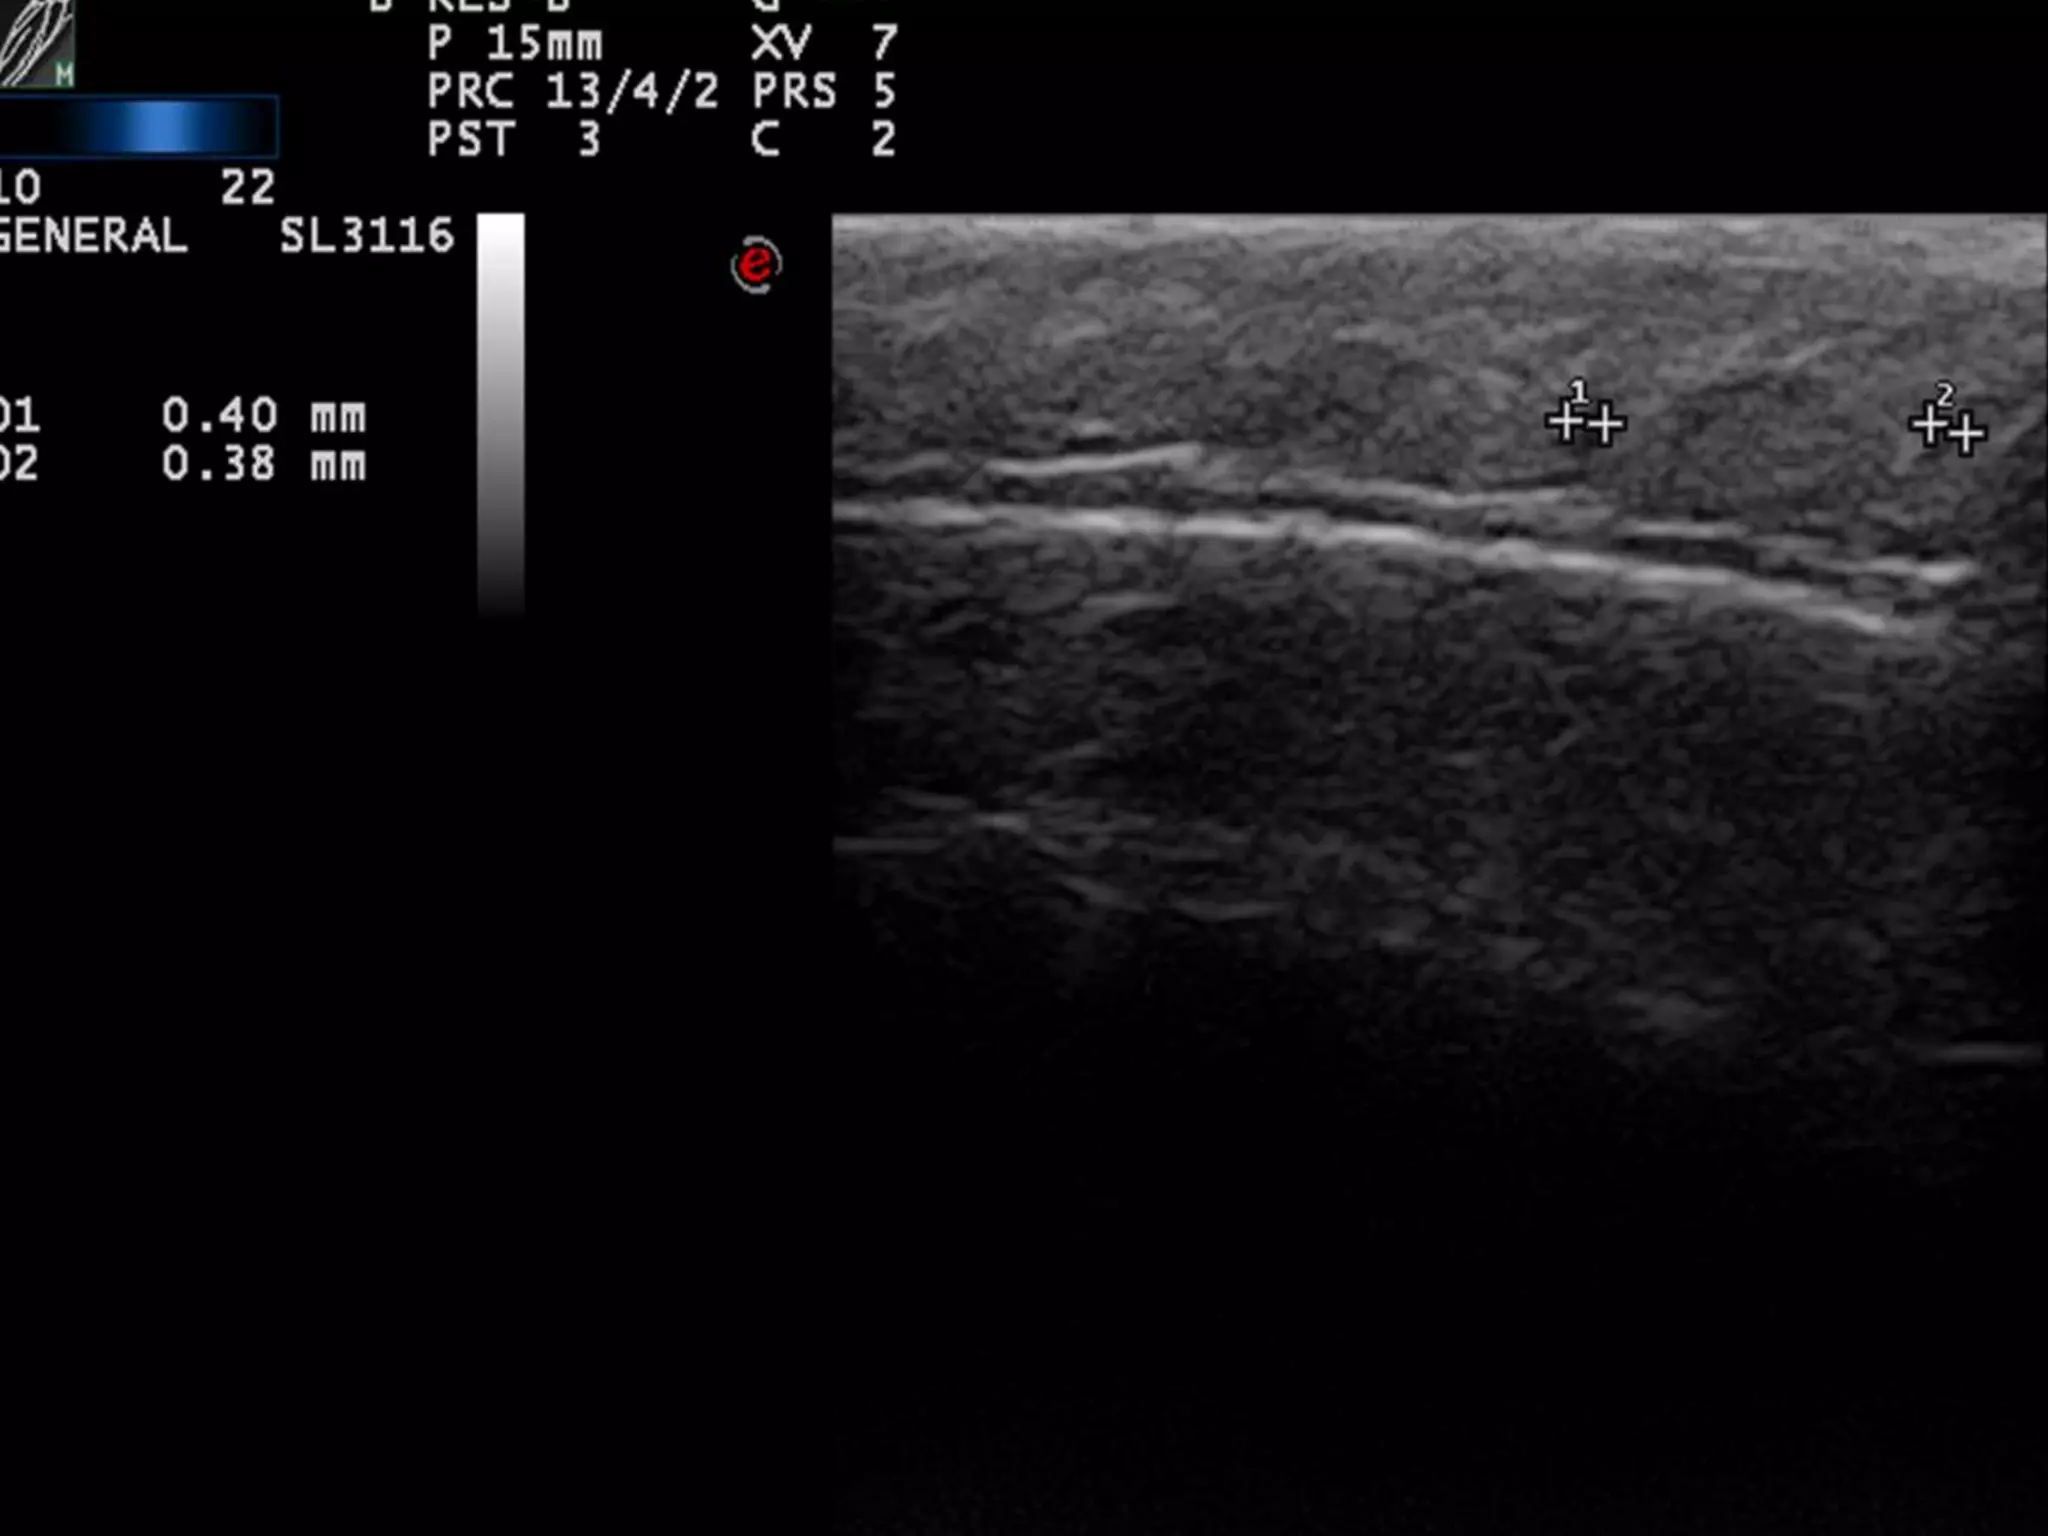

REGLAS “FÁCILES”

PARA DETECTAR INFLAMACION

1)La estructura inflamada se suele hacer

Hipoecoica = edema+células

2)El flujo Doppler Suele estar aumentado=

Aumento de flujo sanguíneo

3) COMPARAR, COMPARAR, COMPARAR